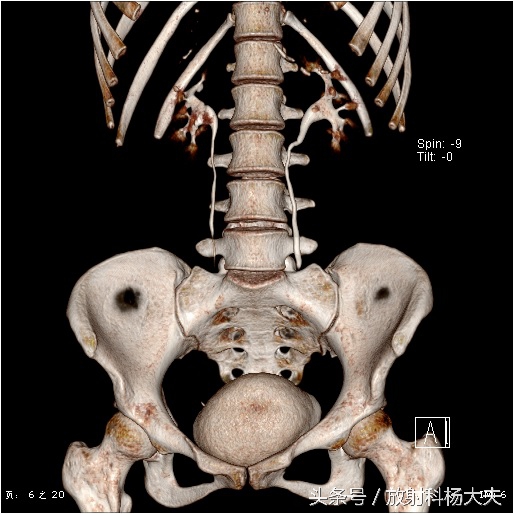

女孩的肾功能是好的,可以看到VR图像里双肾盂和输尿管显影很清楚。